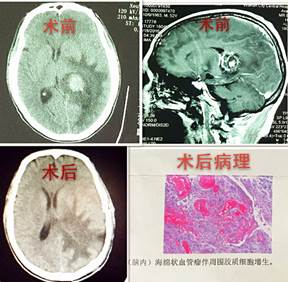

神外二病区成功切除脑深部海绵状血管瘤

近日,神经外科二病区在白西民主任医师的主持下完成了脑深部海绵状血管瘤切除术,患者已痊愈出院。

患者吕某,男,52岁,渭南华州区人,患者入院时自诉头痛12天,入院后行检查颅脑CT提示:左侧侧脑室后角占位,周围伴水肿。入院诊断为左侧侧脑室占位性病变。我市神经外科首席专家白西民主任医师高度重视,积极进行术前准备,在赵云洁住院医师的配合下在全麻下行左侧侧脑室肿瘤切除术,手术顺利。术后病理报告为:脑深部海绵状血管瘤伴胶质增生。患者术后头痛好转,无神经功能障碍。

脑内海绵状血管瘤也称海绵状血管畸形,或称海绵状瘤,多伴有癫痫、出血和局部神经功能缺损症状。此患者肿瘤位于侧脑室,位置较深,且毗邻重要结构,手术路径长,周围脑组织水肿广泛,颅内压高,手术难度较大,因此手术者必须具备扎实的神经外科解剖知识和熟练的显微外科技术。本例手术在神经外科二病区医务人员的努力下成功切除肿瘤,患者没有神经功能缺损,效果良好。

(神经外科二病区:党俊涛供稿)